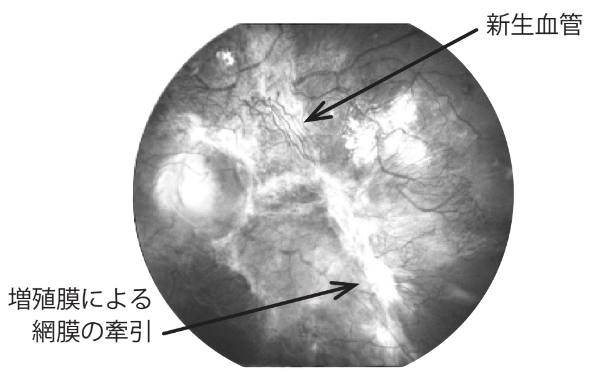

糖尿病網膜症が進行すると、網膜の血のめぐりが悪くなり、網膜に新しい血管(新生血管)が発生したり、膜状の組織(増殖膜)が網膜を引っ張って「網膜剥離 」を起こすこともあります。

この他に、黄斑に水が溜まって「黄斑浮腫」を起こすこともあります。

進行した糖尿病網膜症の例(左眼)